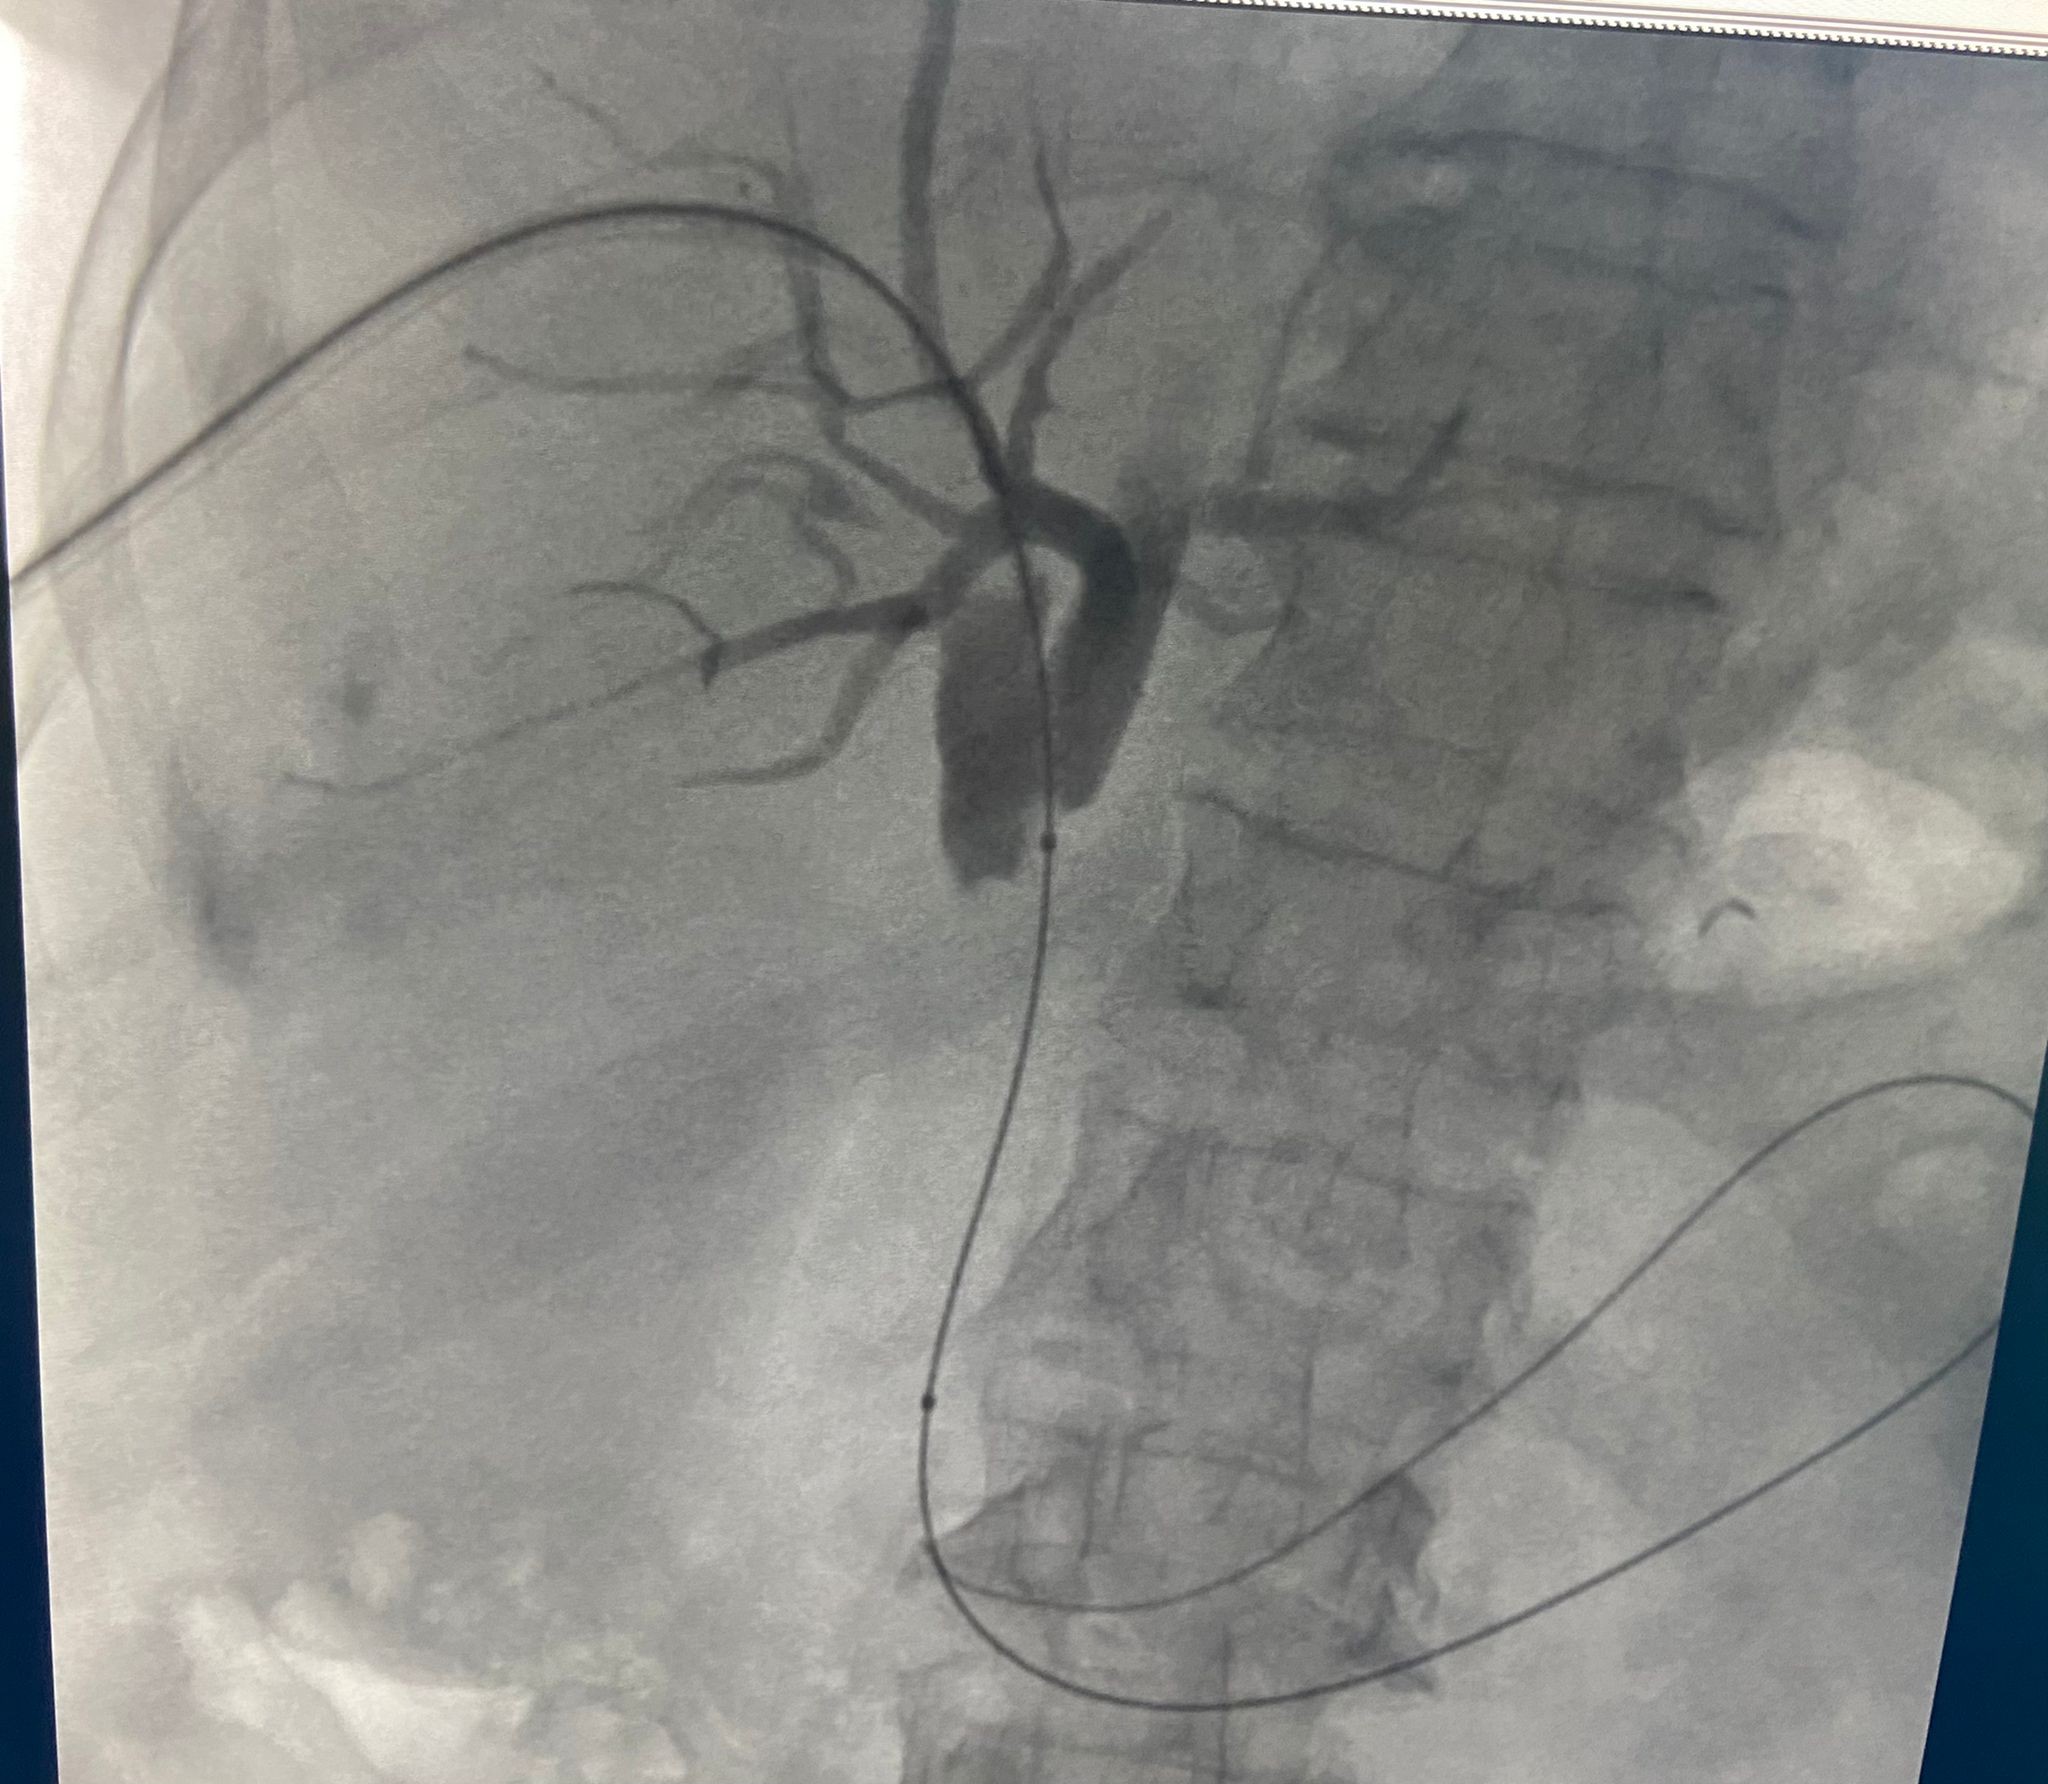

Prof. Dr. Ercan Kocakoç, bu yeni yöntemin tıp literatürüne Radyofrekans (RF) ablasyon olarak geçtiğini belirtti. Başta karaciğer olmak üzere vücudun birçok bölgesindeki tümörlerin ultrason, tomografi gibi görüntüleme yöntemlerinin kılavuzluğunda yakılarak tedavi edebilen, girişimsel radyolojik bir yöntem olduğunu söyledi. Prof. Dr. Ercan Kocakoç, önce safra kanalı içerisine basitçe ince plastik bir hortum yerleştirilerek, biriken safra sıvısının dışarıya alındığını dile getirerek, “Tümörün olduğu bölgedeki darlık, bir tel yardımıyla geçilebilirse önce balon ile bu bölge genişletilmeye çalışılır. Sonrasında ise stent denilen ince tellerden örülü metalik bir küçük borucuk yerleştirilerek dışarıda hortum olmadan safranın on iki parmak barsağına akması sağlanır” dedi.

Prof. Dr. Ercan Kocakoç ayrıca safra yolu kanserlerinin tedavisinde Endobiliyer RF ablasyon yöntemi ile de safra kanalı içerisindeki tümörün RF ablasyon ile yakıldığını kaydederek, “Bu yöntemde safra kanalındaki darlığın balon ile açılması, safra kanalı içerisinden RF (radyofrekans) ablasyon ile tümörün yakılması ve safra kanalına metalik stent yerleştirilmesi aşamaları vardır. Bu işlem safranın on iki parmak bağırsağına akmasını sağlayarak sarılıksız daha uzun bir ömür geçirilmesine katkı sağlar” şeklinde konuştu.

Prof. Dr. Ercan Kocakoç en son, 75 yaşında yurtdışından sarılık şikâyeti ile gelen, ana safra kanalında tümör bulunan ve ciddi kalp yetmezliği nedeniyle ameliyatı riskli olan bir hastasına bu yöntemi başarıyla uyguladıklarını dile getirdi. Yaklaşık 11 ay önce genel anestezi verilmeden sedasyon ile endobiliyer RF ablasyon tedavisi ve stent yerleştirilmesi işleminin gerçekleştirildiğini açıkladı. Sarılığı yaklaşık 1 hafta içerisinde normale dönen hastamız halen sarılık şikâyeti olmaksızın hayatına devam etmektedir.